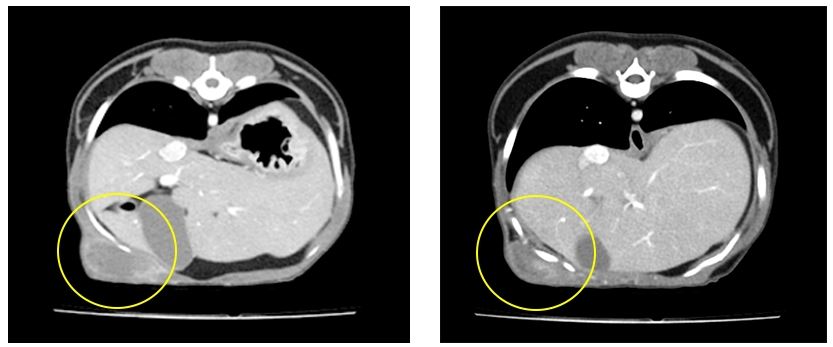

조직 검사&CT 검사

조직 검사를 진행하여 정확한 종양의 종류를 평가하였는데 안타깝게도 결과는 악성 연부 조직( soft tissue sarcoma ) 으로 나왔습니다.

악성종양으로 나왔기 때문에 수술적인 제거가 불가피하고 완전히 제거 가능한지 또 정확한 전이 평가를 위해 CT 촬영을 진행했습니다.

CT 검사 결과 상 악성 연부 조직 종양은 흉곽을 이루고 있는 갈비뼈 사이 근육과 복벽을 이루고 있는 근육이 결계가 불명확하다는 결과를 얻었습니다.

여기서 종양을 수술적으로 완전 제거, 절제 한다고 할 때에는 종양과 그 종양을 둘러싼 정상 조직을 포함해 제거할 경우 완전 절제가 되었다고 말할수 있으며, 종양의 종류에 따라 주변으로 침습되는 정도가 다르기 때문에 종양과 정상조직의 포함하는 정도가 다른데, 뿌꾸의 악성 종양은 정상 조직을 포함해서 제거를 하려면 흉강과 복강의 재건이 필요한 아주 큰 수술이 필요했고 침습적인 수술보다는 종양을 최대한 제거한 후 항암치료를 병행하는 쪽으로 수술이 진행되었습니다.